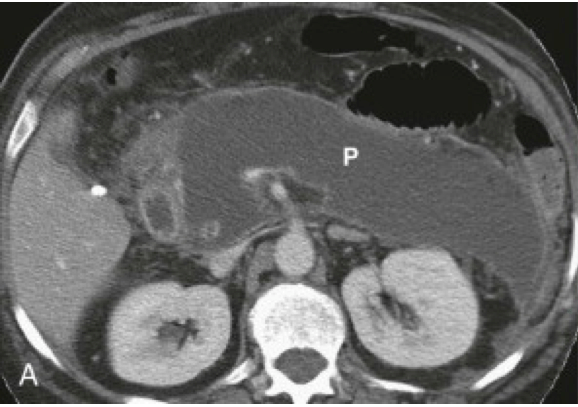

Na prijemu pacijenta možemo uraditi RTG abdomena, ali zlatni standard je CT!